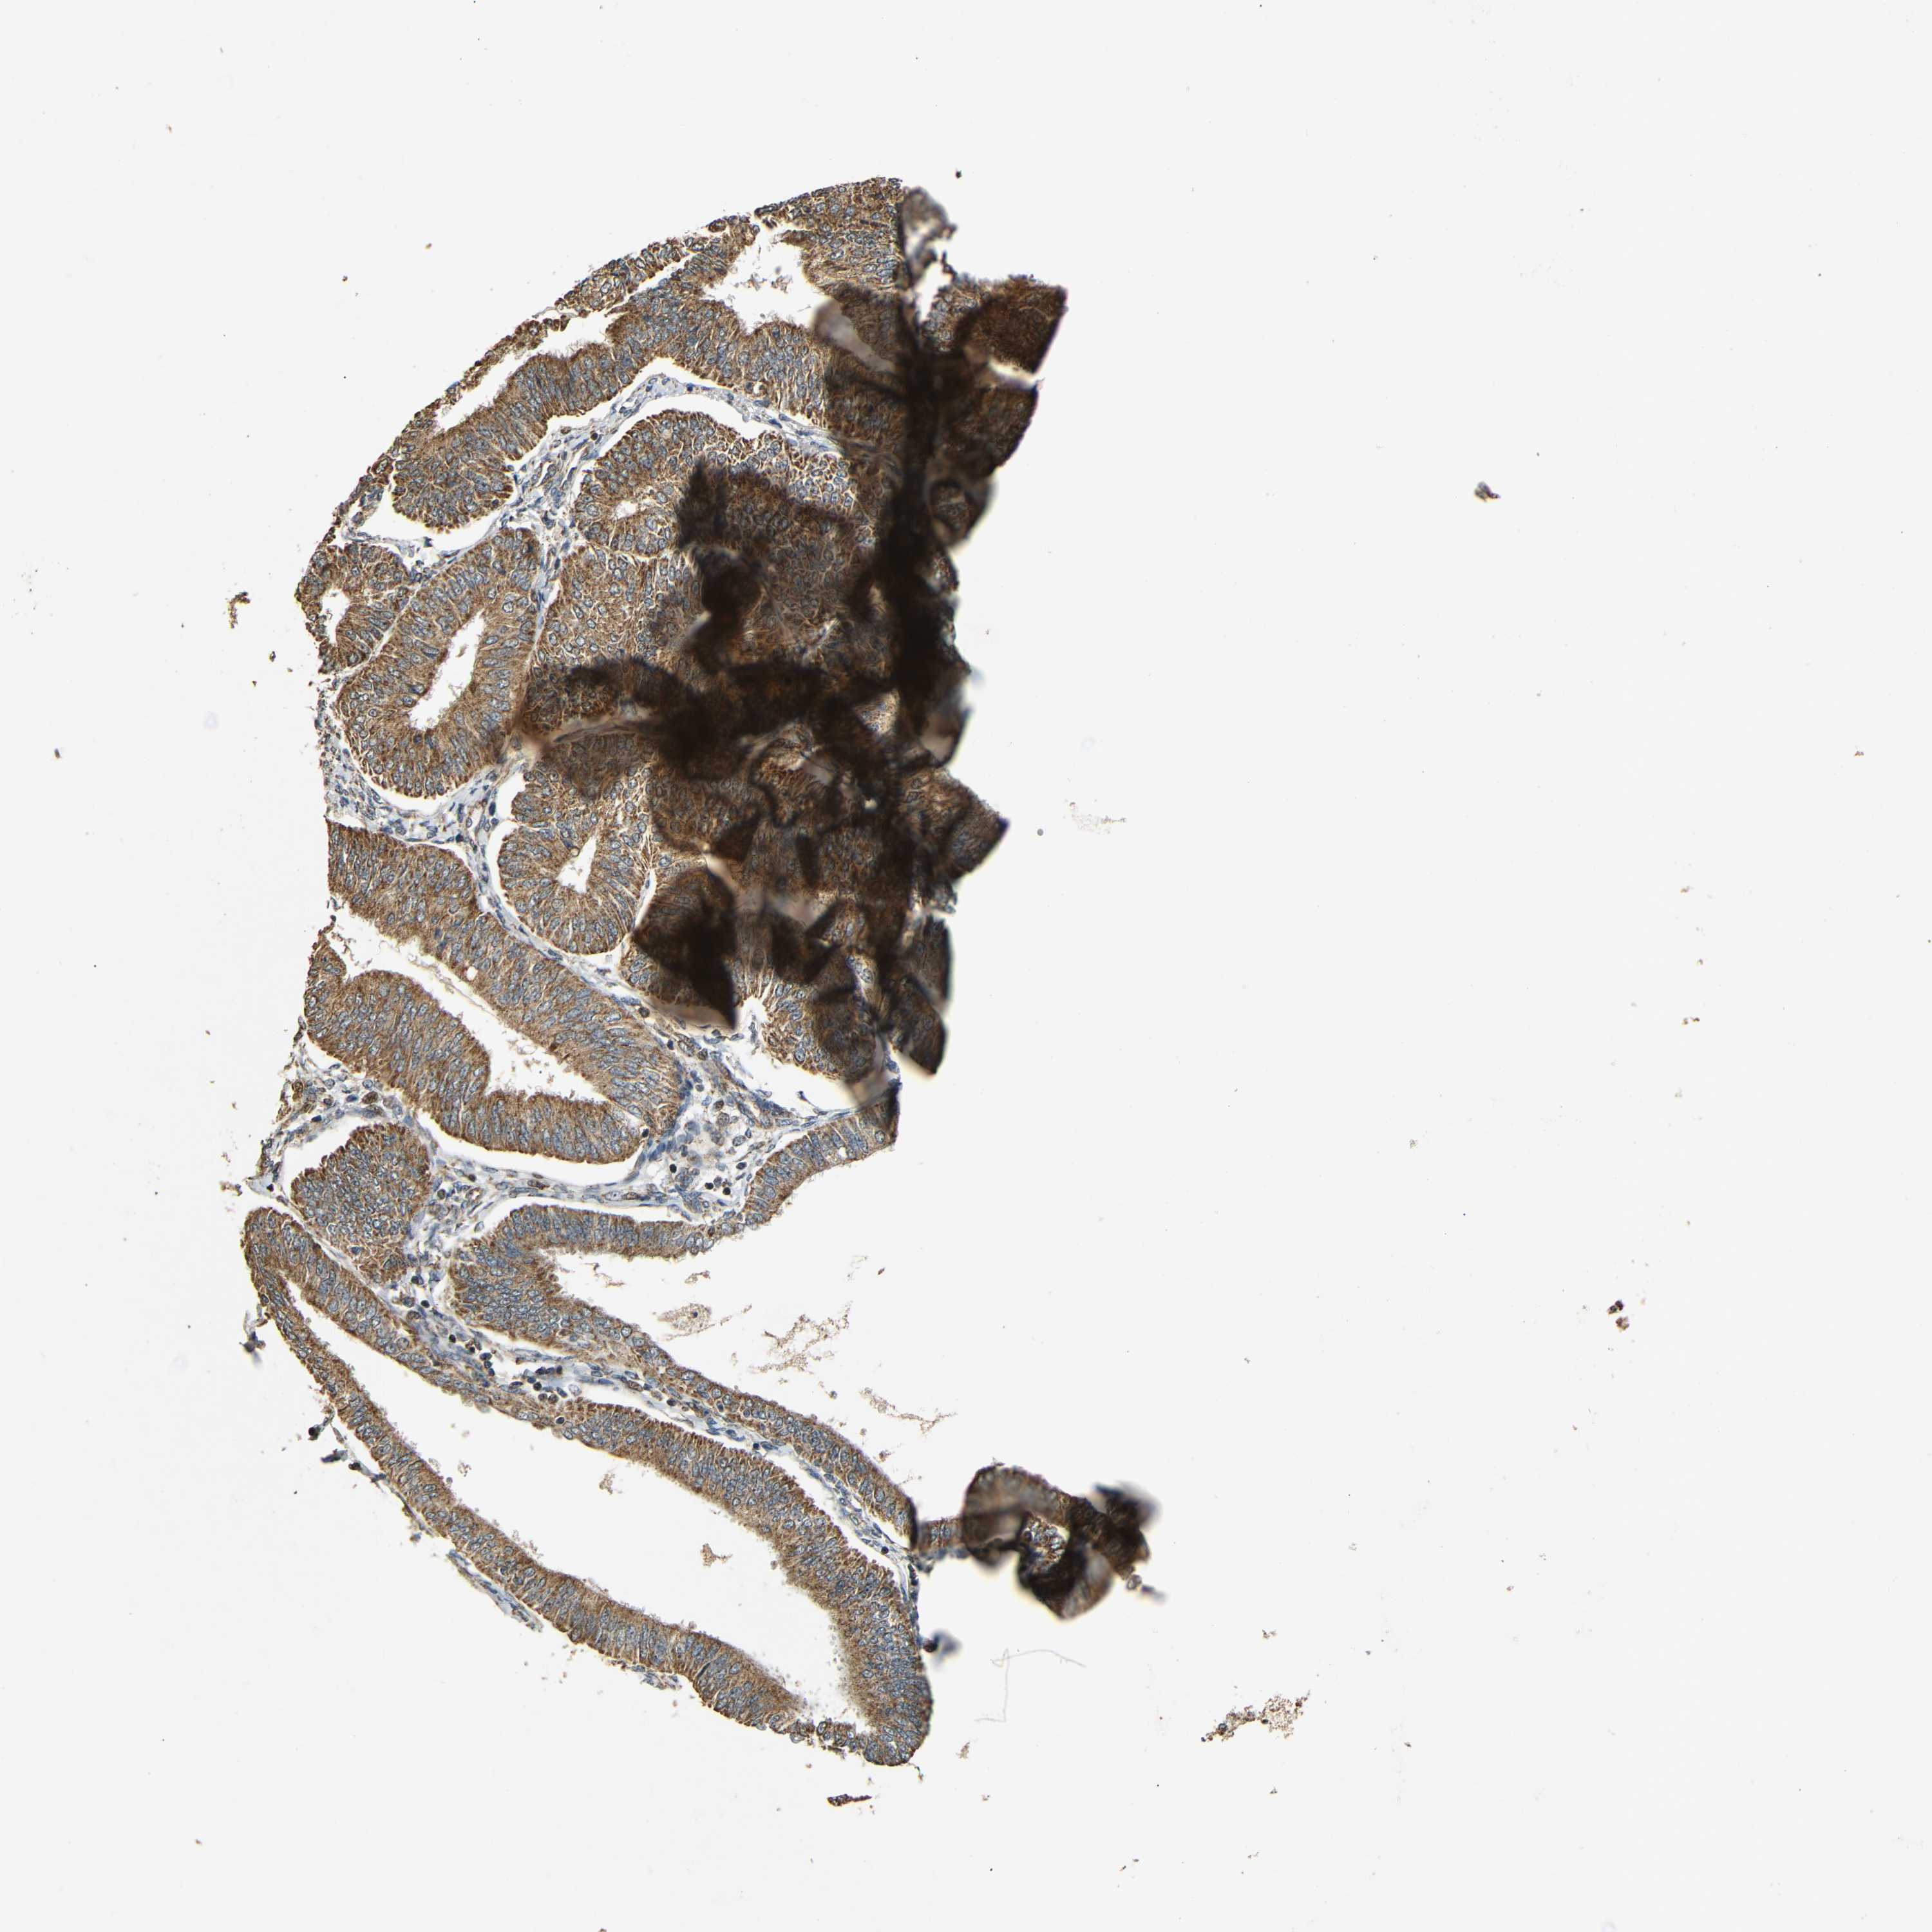

ENDOMETRIAL CANCER - Protein expressioni

A mouse-over function shows sample information and annotation data. Click on an image to view it in a full screen mode. Samples can be filtered based on level of antibody staining by selecting one or several of the following categories: high, medium, low and not detected. The assay and annotation is described here.

Note that samples used for immunohistochemistry by the Human Protein Atlas do not correspond to samples in the TCGA dataset.

Antibody stainingi

Antibody staining in the annotated cell types in the current human tissue is reported as not detected, low, medium, or high, based on conventional immunohistochemistry profiling in selected tissues. This score is based on the combination of the staining intensity and fraction of stained cells.

Each image is clickable and will lead to virtual microscopy that enables deeper exploration of all samples and also displays staining intensity scores, fraction scores and subcellular localization as well as patient and tissue information for each sample.

Antibody HPA011800

Staining

High

Medium

Low

Not detected

Intensity

Strong

Moderate

Weak

Negative

Quantity

>75%

75%-25%

<25%

None

Location

Nuclear

Cytoplasmic/membranous

Cytoplasmic/membranous,nuclear

Adenocarcinoma, NOS